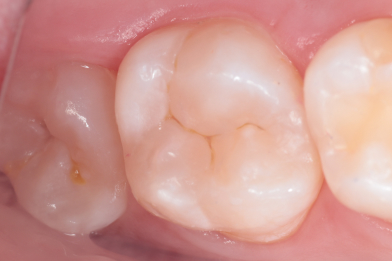

Д.12 лет. Жалобы на реакцию, на сладкое и холодное между зубами 16,15.

Колиш Максим Петрович

При осмотре обнаружен контактный кариес на зубах 16,15.

Лечение в один визит, восстановление функциональности композитной реставрацией. -